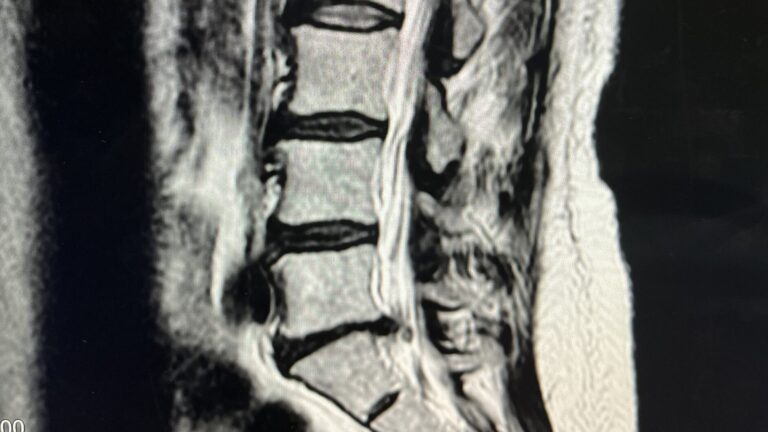

重度の頚椎ヘルニアの症例

重度の頚椎ヘルニア・肩から指までの痛みと痺れの症例 【大阪市 70代男性】 30年間接骨院に通院していましたが、頭痛と肩こりに加え腕の痛みと痺れが取れず、最近は腕も細くなってきたので整形外科へ。MRI…